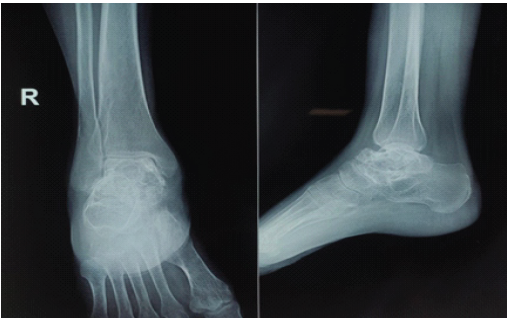

A 32-year-old female presented with complaints of pain and swelling in the dorsum of her foot. The swelling was insidious in onset and was noticed by the patient while bathing and was the size of a pea. It was associated with pain, which was insidious in onset, dull aching in nature, mild to moderate in intensity, with no aggravating or relieving factors, not radiating to any other site, and not relieved by rest. There was no history of trauma as well. Clinical examination revealed the swelling to be hard, attached to the underlying structure, not attached to the overlying skin, non-mobile, non-tender and with no erythema or local rise of temperature. There was no appreciable change in size since the patient had first noticed the swelling. X-rays and magnetic resonance imaging (MRI) were advised to the patient for the same and conservative management was advised (Fig. 1, 2).

Figure 1: Radiograph of right foot of the patient in anteroposterior and lateral view, showing multiple cystic lesions of the talus.

X-Rays of the foot of the patient showed a lytic lesion of the right talus bone. A contrast-enhanced MRI was also advised, which showed a large irregular multiloculated expansile cystic lesion, measuring approximately 4.1 × 3.1 × 2.2 cm, involving the talar dome and neck reaching up to the anterior articular surface. The lesion appeared as heterogeneously hyperintense on T2/Short tau inversion recovery images and iso to hypointense on T1-weighted images with multiple intrinsic thick enhancing septae causing loculation with multiple intrinsic blood-fluid levels, suggestive of ABC, and histopathological and clinical correlation was advised. Upon follow-up, image-guided fine needle aspiration cytology (FNAC) and biopsy of the patient were done. The FNAC was suggestive of few scattered multinucleated giant cells along with few degenerated cells against hemorrhagic background, likely a benign lesion (Fig. 3). The biopsy result reported fragmented bone tissue with hemorrhagic cystic spaces lined by osteoclastic giant cells and mononuclear cells with mild anisonucleosis with two possible differentials: Giant cell tumor and ABC, both being quite rare in the talus.